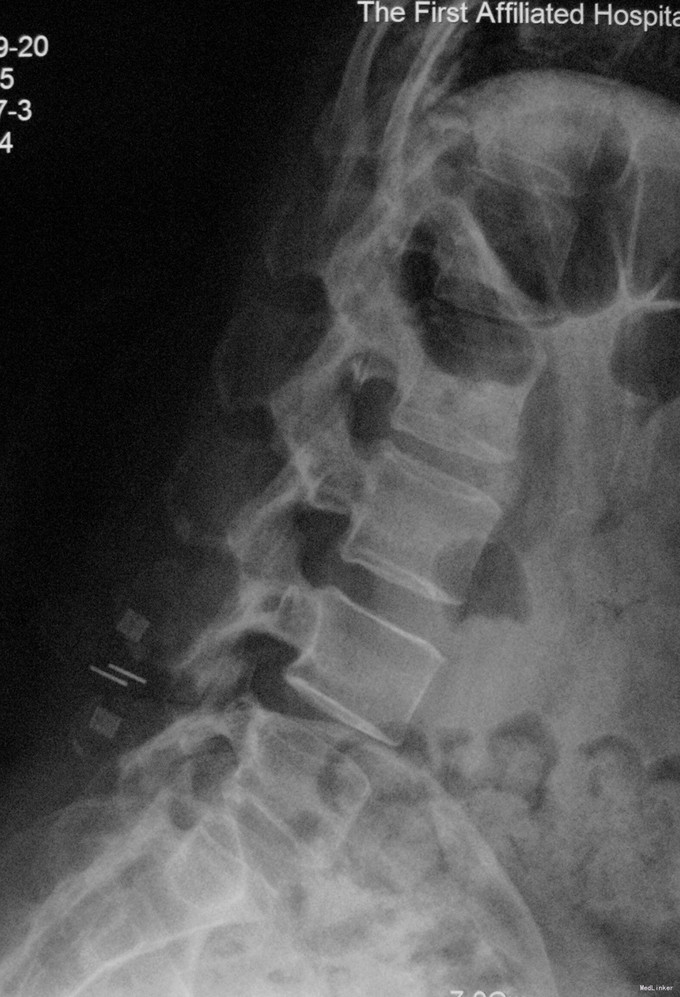

诊断:腰4/5椎管狭窄并失稳症。 治疗:给予行后路腰4/5右侧椎板间开窗减压椎间盘摘除并肥厚黄韧带切除+棘突间wallis固定术。

随访示患者腰痛及双下肢跛行症状明显缓解。 讨论:该例患者临床症状主要为腰痛并间歇性跛行,椎间盘突出合并黄韧带肥厚致椎管狭窄,且存在轻度失稳,故给予椎管减压并棘突间wallis动态固定。术后效果满意。